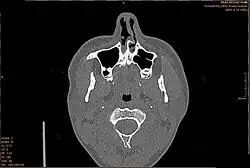

CT-Aufnahme, Septumdeviation

Die Diagnose einer Septumdeviation wird mittels äußerer Inspektion der Nase, vorderer Rhinoskopie, Endoskopie oder Computertomografie (CT) gestellt. Wie stark eine Septumdeviation die Nasenatmung behindert, kann mithilfe einer Rhinomanometrie gemessen werden. Außerdem sollte eine Riechprüfung durchgeführt werden.